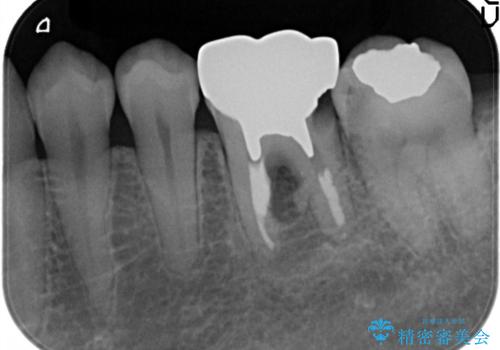

樋状根(といじょうこん)の根管治療